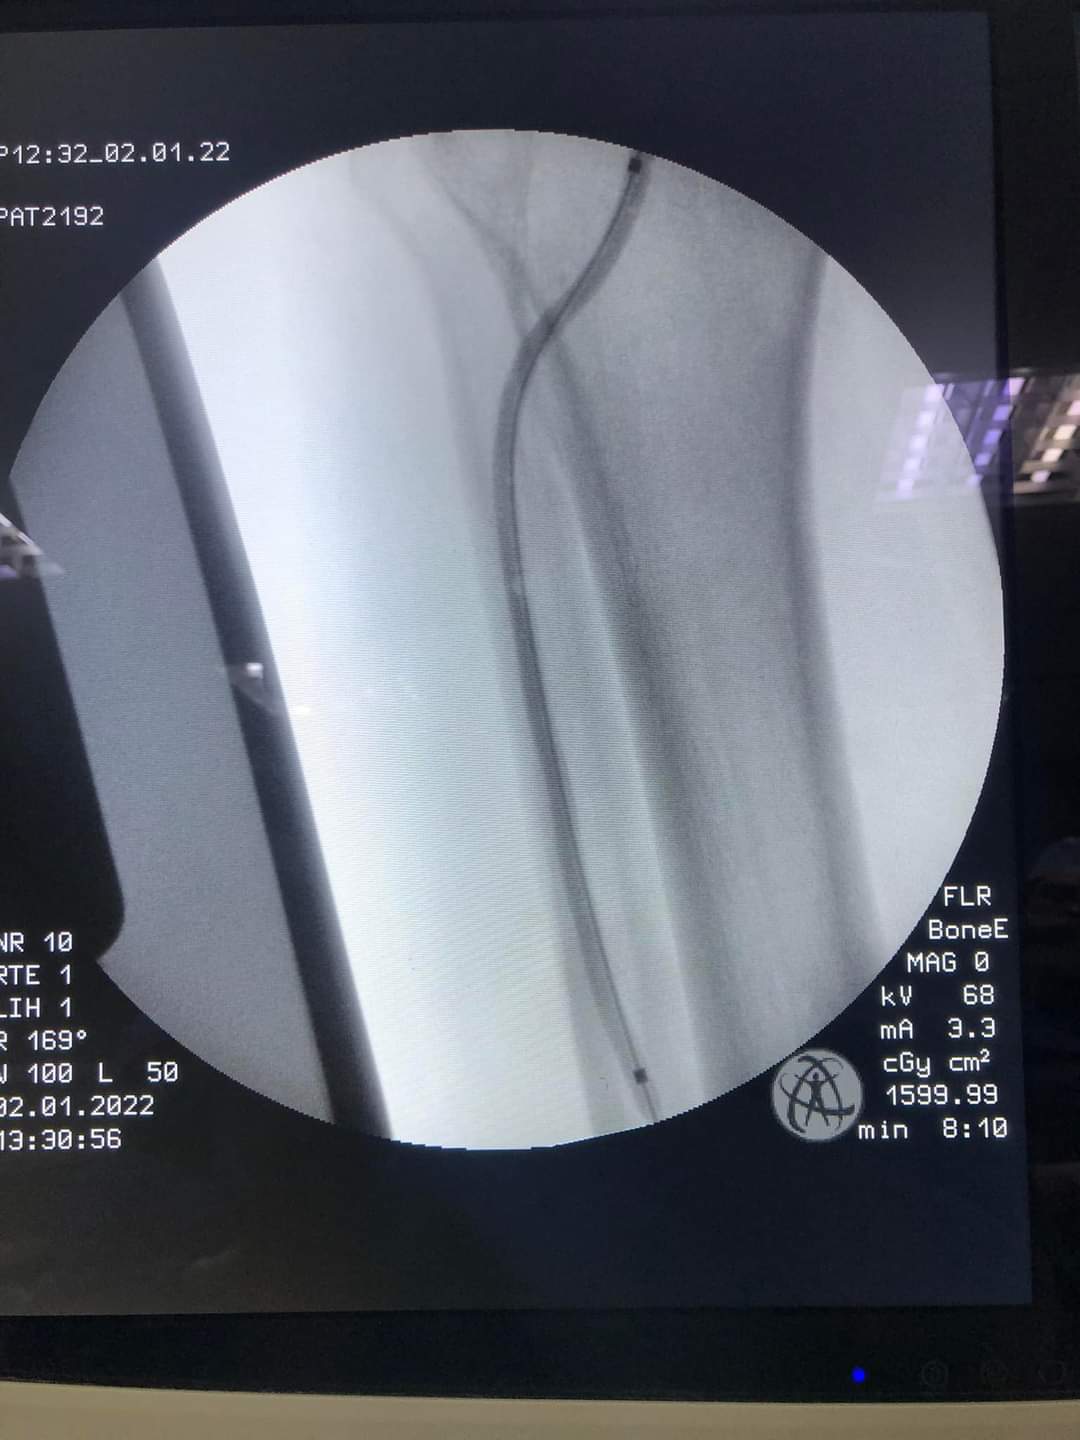

اوضح الدكتور جمال سلامة ان اول هذه العمليات كانت توسيعا للشرايين الطرفية للطرف السفلي الأيمن بواسطة بالون توسيع وبالون دوائي لوجود قصور بالشرايين المغذية للطرف السفلي الأيمن وقام بإجرائها الدكتور محمد حمزة استشاري جراحة الأوعية الدموية بالمستشفى وثانيها كانت توسيعا للأوردة المركزية والطرفية للطرف العلوي الأيمن لوجود انسداد بها في مريض فشل كلوي مزمن وقام بإجرائها الدكتور عمرو عبد الموجود استشاري جراحة الأوعية الدموية بالمستشفى وكان ختامها مسك بعد النجاح في إجراء واحدة من اكثر العمليات تعقيداً في هذه الفئة وكانت في مريض يعاني من انسداد كامل بالشريان الحرقفي الأيسر مع الشريان الفخذي الأيسر وذلك بوضع دعامتين للشريانين الحرقفيين وذلك باستخدام القسطرة التداخلية من خلال الفخذ الأيمن والذراع الأيسر وقام بإجرائها الدكتور محمد حمزة استشاري جراحة الأوعية الدموية بالمستشفى.